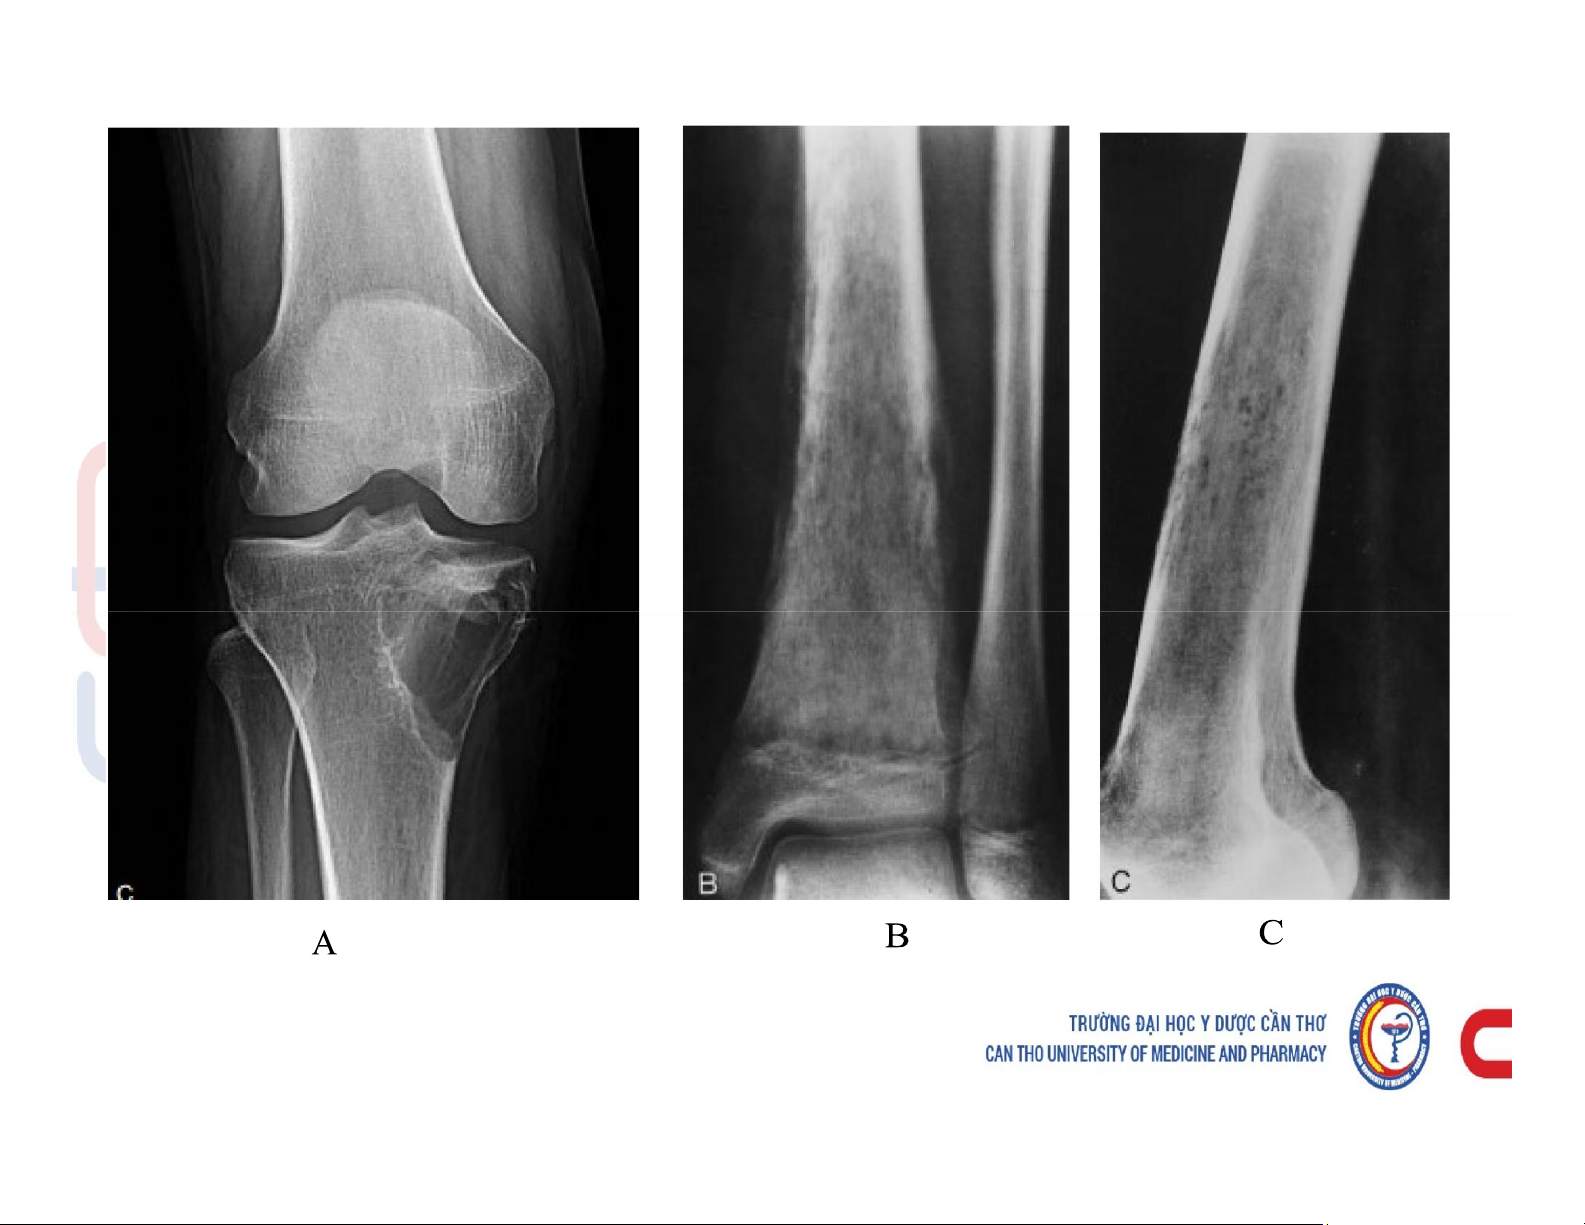

Mô tả và chú thích được các cấu trúc giải phẫu x quang xương khớp. Mô tả các dấu hiệu cơ bản trên phim x quang xương khớp. Phân tích được hình ảnh x quang bệnh lý của một số nhóm bệnh lý xương khớp. Các dấu hiệu cơ bản của phim. Tài liệu giúp bạn tham khảo, ôn tập và đạt kết quả cao. Mời đọc đón xem!